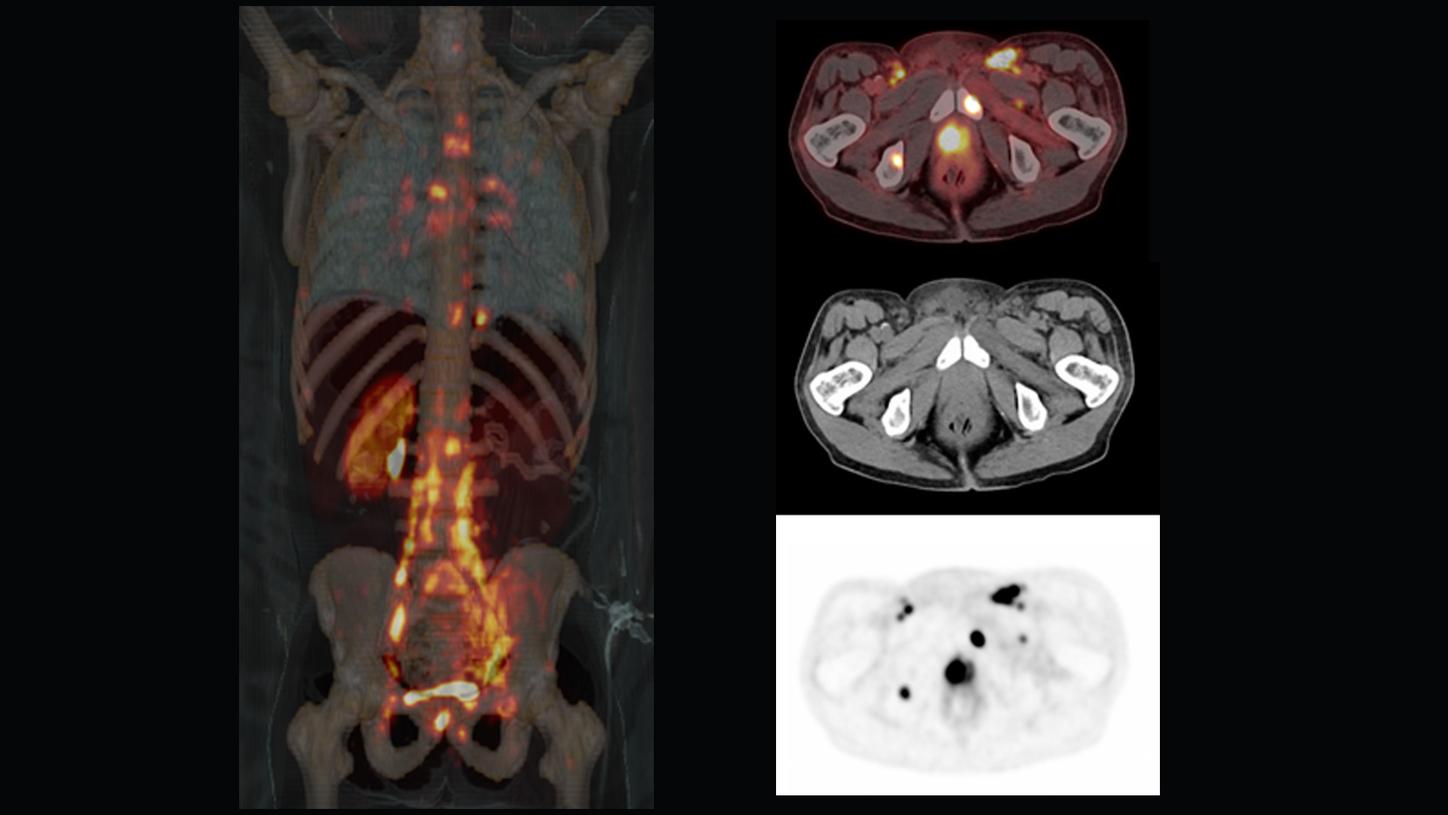

Answering to clinical needs in oncology, neurology, cardiology, and radiology, Siemens Healthineers Molecular Imaging systems provide PET/CT, SPECT, and hybrid SPECT scanner (SPECT/CT) solutions to help clinicians diagnose, treat, and monitor diseases more confidently.